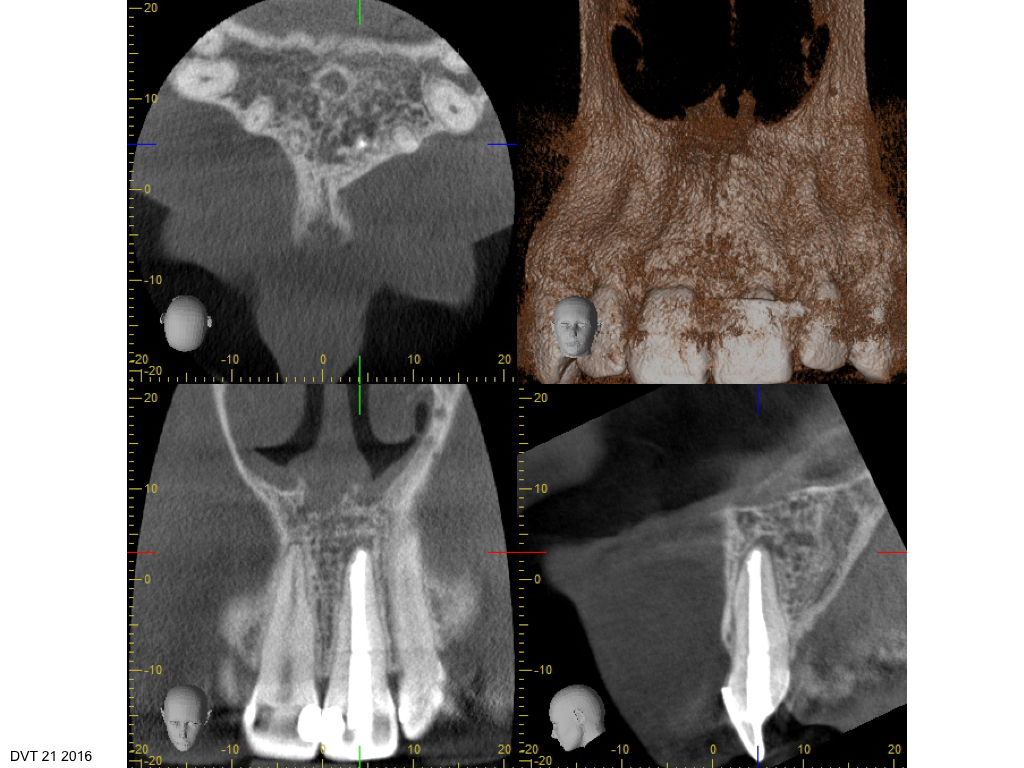

RECALL – Hätten Sie es gesehen?